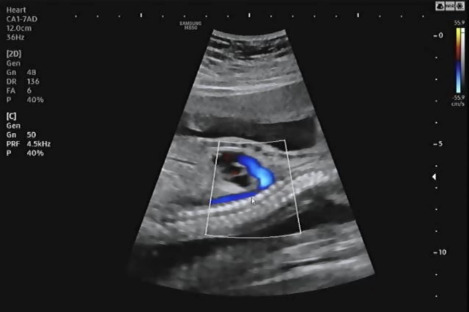

복부를 보고 장기가 주수에 맞게 잘 발달하고 있는지 확인했다. 심장, 간, 위 등 현재 잘 있는지 확인하고 심장에서 혈류가 잘 흐르고 있는지 확인했다. 심장이 심실 2, 심방 2로 잘 나뉘어 있는지 혈류가 알맞게 흐르고 있는지 확인하는데 신기했다. 혈류가 알맞게 제 방향으로 흐르는 것을 확인하고 태아의 심장이 잘 뛰고 있는지 확인했다.